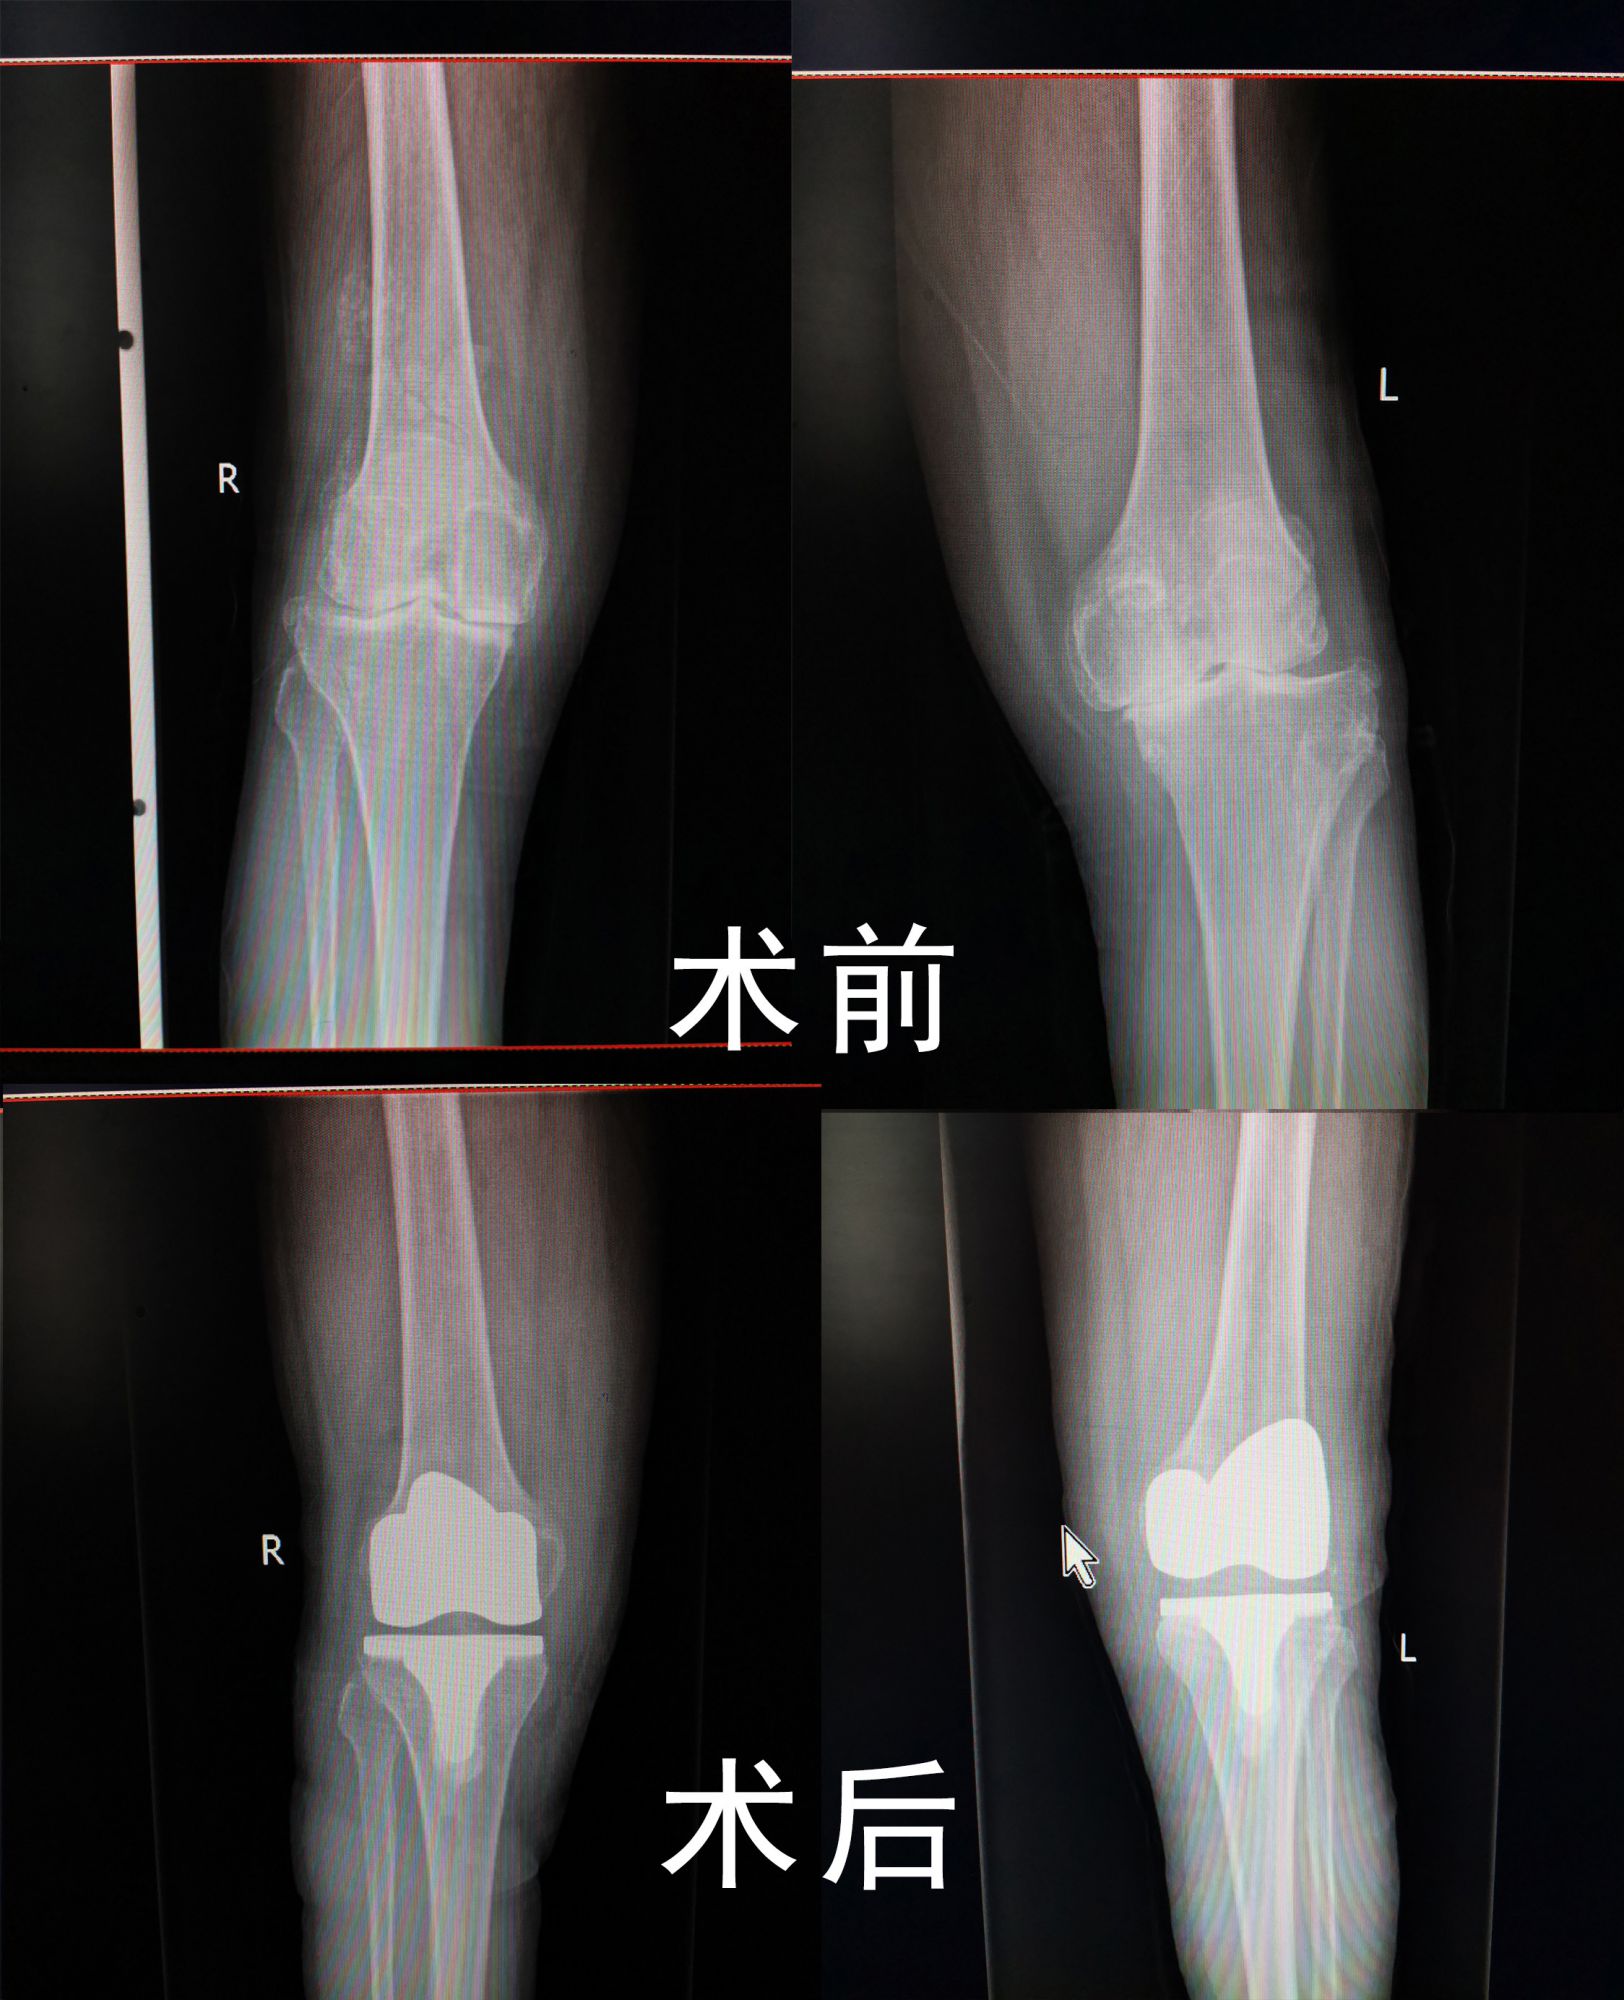

11月27日,70多岁的田奶奶因“双膝疼痛10年,加重两年”来院就诊。入院检查显示双膝关节严重退行性变,内翻畸形,药物治疗无效,为了从根本上解决关节病变,进行手术治疗。术后第二天田奶奶就能正常下地活动了。

人工膝关节置换就是利用人工的膝关节假体去替代磨损的膝关节软骨的表面,手术中医生需要切开皮肤、皮下直至关节囊,去掉受损的关节软骨及骨组织。